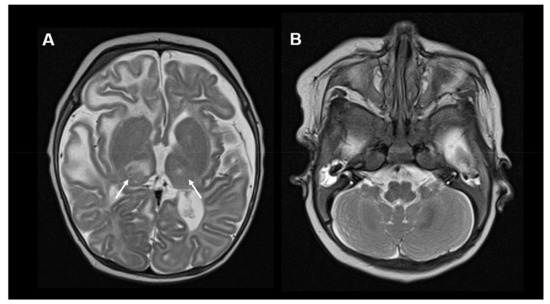

An example of imaging findings in COQ7 deficiency is depicted in Figure 4.

Figure 4.

Neuroimaging in COQ7 deficiency: (A) Brain MRI, T2-weighted, axial images of a 10-month-old boy with COQ7 deficiency. The MRI shows global brain atrophy and areas of encephalomalacia in bilateral frontal lobes. In addition, symmetric cystic changes within the putamen are visible (white arrows). (B) No cerebellar abnormalities are visible. Other MRI images of this individual were published previously [41].